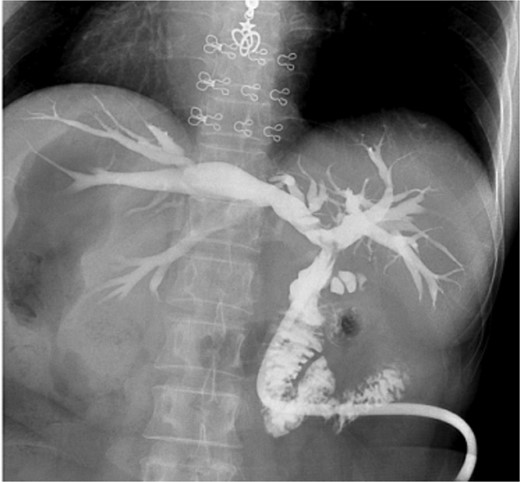

Intraoperatively, the liver was located on the left side, with the spleen and stomach on the right. The surgeon stood on the patient’s right side, with the patient in a reverse Trendelenburg position (30° head-up, 15° left-side down). Adhesions between the liver, omentum, and surrounding organs were carefully dissected to expose the common bile duct, which measured 2.0 cm in diameter. A 1.5 cm longitudinal incision was made on the common bile duct, and stones were extracted using atraumatic forceps and a stone retrieval basket. Choledochoscopy confirmed no residual stones in the intrahepatic or extrahepatic bile ducts. Due to marked edema at the lower end of the common bile duct caused by stone impaction, a 22 French T-tube was placed. The procedure lasted 125 minutes, with no postoperative bile leakage or other complications. The patient had an uneventful recovery and was discharged on postoperative day 5. Two weeks later, cholangiography showed no residual stones in the bile duct (Fig. 3).

Postoperative cholangiography shows no residual stones in the bile duct.